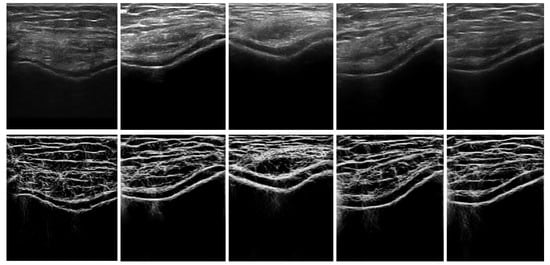

Qualitative results of the automatically segmented cartilage regions using the three different automatic segmentation methods and the manual expert segmentations are shown in Figure 7. Investigating the results, we can infer that the RW algorithm yielded better cartilage segmentation, whereas the watershed and graph-cut algorithms are limited by over- and undersegmentation for various cartilage sections. Figure 8 shows the qualitative results of cartilage segmentation obtained when the original B-mode images were used as an input to the segmentation methods. Qualitative results show that the RW algorithm yielded better cartilage segmentation, whereas watershed and graph-cut were limited by oversegmentation. Comparing the qualitative results, shown in Figure 7 and Figure 8, we can see the improvements achieved in segmentation quality when using the enhanced US images as an input to the investigated segmentation methods.

Figure 8.

Top row: Qualitative results of automatically segmented cartilage using B-mode US data as an input to the segmentation method, overlaid on expert manual segmentation (red: false negative, magenta: false positive, white: true positive): (a) Manual segmentation overlaid with RW segmentation. (b) Manual segmentation overlaid on watershed segmentation. (c) Manual segmentation overlaid on graph-cut segmentation. Bottom row: automatically segmented cartilage region overlaid on original B-mode US data: (d) Cartilage region segmented using RW method. (e) Cartilage region segmented using watershed method. (f) Cartilage region segmented using graph-cut method.